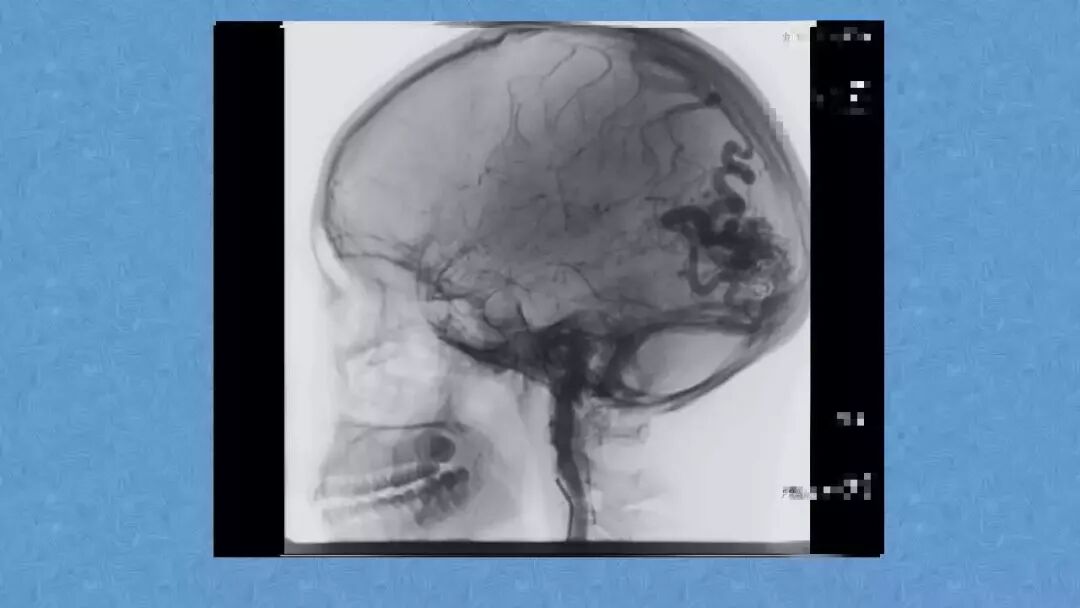

今天为大家分享的是《贝朗时间》第二十九期,湖北十堰市太和医院神经外科张力教授团队带来的:一个AVM患者的48小时纪实,欢迎阅读、分享!

张力教授:AVM切除术